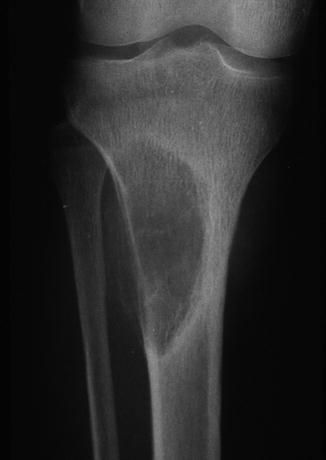

For the critical thinkers ONLY. πŸ€“ what is your diagnosis

A spoiler -> this is a mass which forms due to HPTH 🧩

Browns tumor